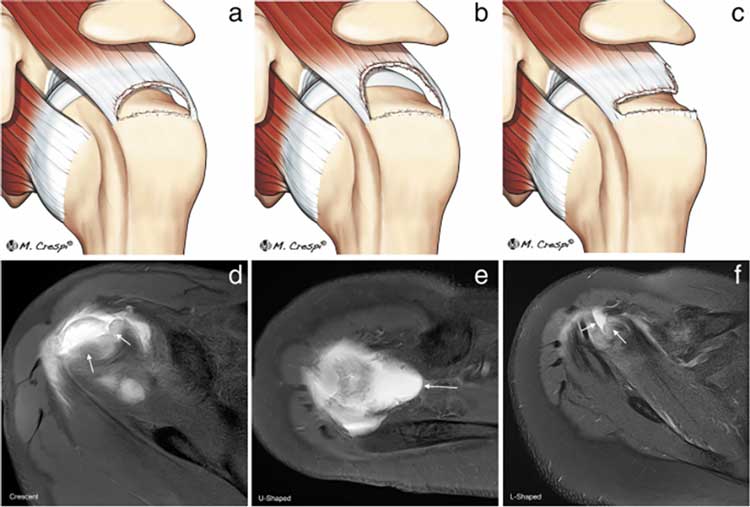

پارگی تاندون شانه به آسیب در عضلات روتاتور کاف اشاره دارد – چهار عضله اصلی (سوپرااسپیناتوس، اینفرااسپیناتوس، ترس ماژور و ساباسکاپولاریس) که بازو را به کتف وصل میکنند و ثبات شانه را حفظ میکنند. این آسیبها دو نوعاند:

پارگی جزئی (کمتر از نصف تاندون) و پارگی کامل (جدا شدن کامل تاندون). این مشکل در مشاغلی مثل نقاشی، بنایی یا ورزشهای راکتی شایع است و علائمش شامل درد شبانه، ضعف در بلند کردن دست و محدودیت حرکت است. درمان اولیه معمولاً غیرجراحی است: استراحت، داروهای ضدالتهاب و مهمتر از همه، ورزش.

- پارگی جزئی: این نوع پارگی (کمتر از ۵۰ درصد ضخامت تاندون) معمولاً با درمانهای غیرجراحی مثل فیزیوتراپی، ورزشهای تقویتی و استراحت بهبود مییابد. حدود ۸۰ درصد بیماران با ۶-۱۲ هفته درمان منظم، بهبود کامل یا قابلتوجهی را تجربه میکنند.

- پارگی کامل: این موارد ممکن است نیاز به جراحی داشته باشند، بهویژه اگر تاندون کاملاً جدا شده باشد. با این حال، حتی در این حالت، درمانهای محافظهکارانه ابتدا امتحان میشوند و در ۵۰-۷۰ درصد موارد مؤثرند.